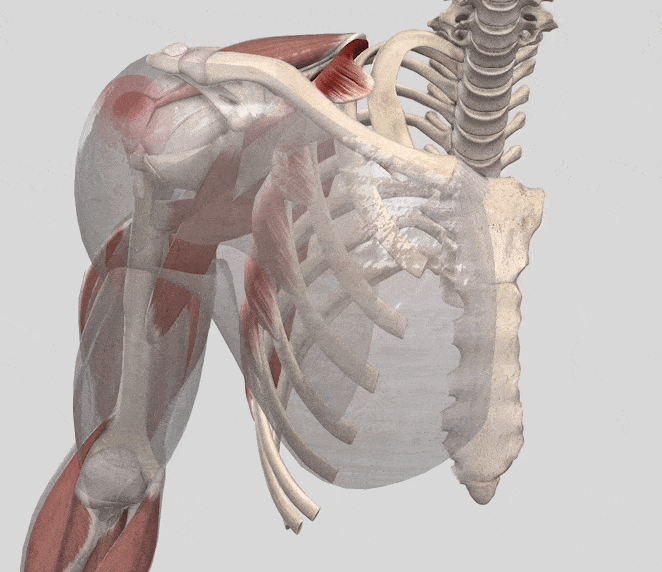

• 腱板損傷

痛みで腕が挙がらない、夜痛みで目が覚める

腱板とは、肩の中にある棘上筋、棘下筋、小円筋、肩甲下筋という4つの筋肉の腱の複合体を言います。スポーツでこの部位を負傷することは多く、腱板損傷とは、肩にある上腕骨頭に付着している腱が骨頭から剥がれたり、破れたりする損傷のことを言います。投球動作の他、ラケット競技、あるいは転倒した際に肩から落ちるなどの外傷が、その原因として挙げられます。

痛みで腕が挙がらない。夜、痛みで目が覚める。腕を下ろす時にも痛みが走る。痛くなったほうの肩を下にして寝られないなどの症状が現れます。

腱板のイラスト